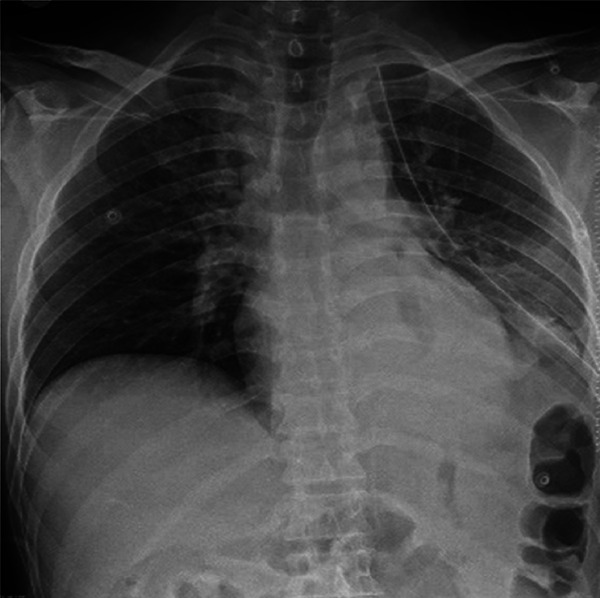

Case presentation: We report the case of a 39-year-old male patient who sustained blunt thoracoabdominal trauma in a motor vehicle accident. The patient presented with respiratory distress and generalized abdominal tenderness. Imaging revealed a left diaphragmatic defect with herniation of abdominal organs into the thoracic cavity.

Outcome: The postoperative course was uneventful. A chest x-ray on postoperative day one confirmed normal diaphragm position and re-expansion of the lung. The patient recovered without complications.